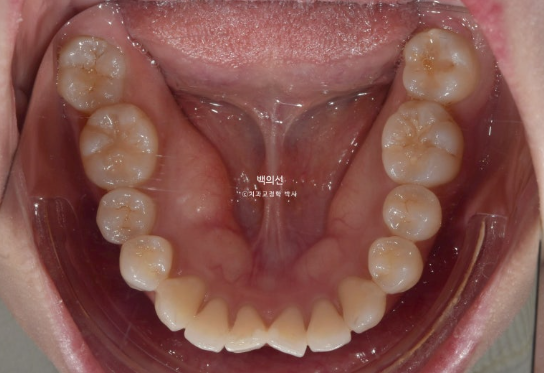

앞니 덧니가 보입니다.

중심선이 약 2mm 어긋나 있습니다.

앞니 뻗침은 심한 편 입니다.

인비절라인을 원하셔서 인비절라인 발치교정을 권유드렸습니다.

작은어금니 4개를 발치하기로 했습니다.

첫번째 세트의 장치는 총 80개가 나왔습니다.